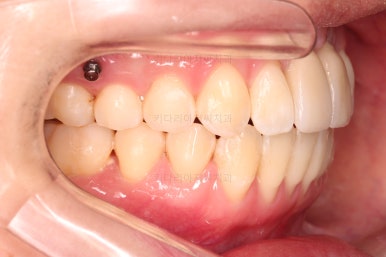

1. 초진

부산개방교합 키다리아저씨치과에 처음 내원 시 입안의 모습입니다.

전반적으로 치열이 삐뚤고요.

앞니쪽이 다물어지지 않는 개방교합(오픈바이트, open bite) 을 보였습니다.

어금니 맞물림을 보면 앵글씨 2급 부정교합 양상이어서 위아랫니가 모두 1대1로 부딪히고 있는 상태였습니다.